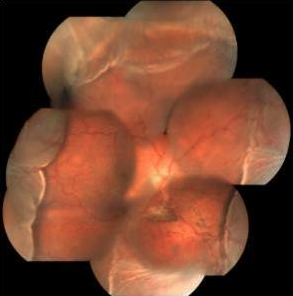

On postoperative day one, the visual acuity was 20/125 but the IOP was non-recordable. There was serous choroidal detachment which proceeded to frank serous retinal detachment superiorly (Figure 2 [Fig. 2]), with visual acuity dropping to counting finger at 2 meters and IOP being still non-recordable. He was treated with topical prednisolone drop at 2-hourly intervals plus oral prednisolone at 1 mg/kg/day dosage. The effusion settled in 2 weeks time after which the steroids were gradually tapered. Gradually the vision and IOP got improved. At the last follow up visit after 3 months, the best corrected visual acuity and IOP were 20/25 and 12 mm Hg off any medication, respectively (Figure 3 [Fig. 3], Figure 4 [Fig. 4]).

Figure 2: Fundus photograph showing combined choroidal detachment and serous retinal detachment superiorly